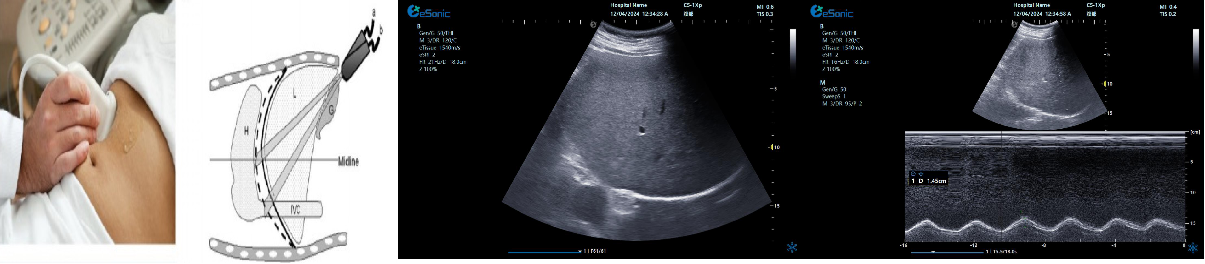

剑突下下腔静脉切面

扫查方法:在剑突下四腔心切面的基础上逆时针调整探头,直至标记指向被检者的头部,轻轻将探头向被检者右边倾斜。

超声声像图:显示右房,下腔静脉及肝静脉,注意观察下腔静脉及肝静脉有无扩张及搏动。